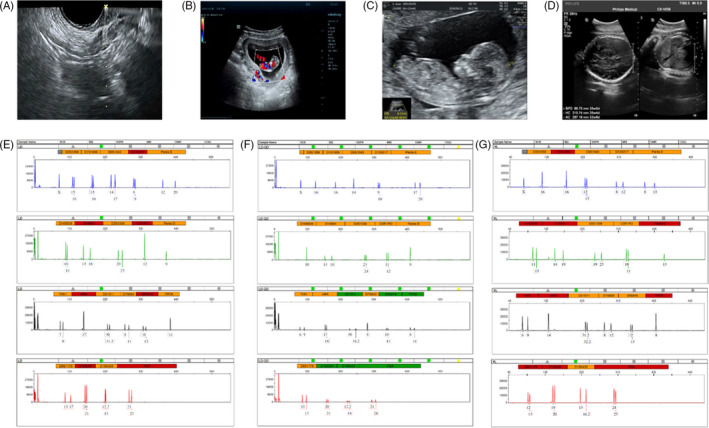

收集了15名接受取卵的患者的基本特征,包括取卵周期、胚胎移植和妊娠次數。一般來說,四個胎兒沒有出生缺陷,三個胚胎來自ICSI的受精類型,而最后一個是自然受孕的。1例術中超聲掃描顯示,在經陰道超聲(TVUS)引導下,卵巢未見間質增生或其他異常卵巢結構(圖2A)。這名婦女在體外受精后成功懷孕,并在第8周進行了基本產前程序的超聲掃描(圖2B),第13周(圖2C) 和第32周 (圖二維) 顯示正常的胎兒發育。微衛星位點分析顯示,胎兒(圖2F)與母親有遺傳關系(圖2E) 供體UCMSC以外的其他人(圖2G)。